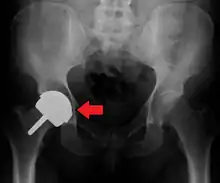

Dislocation

Dislocated artificial hip

Liner wear, particularly when over 2 mm, increases the risk of dislocation.[8] Liner creep, on the other hand, is normal remoulding.[9]

Dislocation (the ball coming out of the socket) is the most common complication. The most common causes vary by the duration since the surgery.